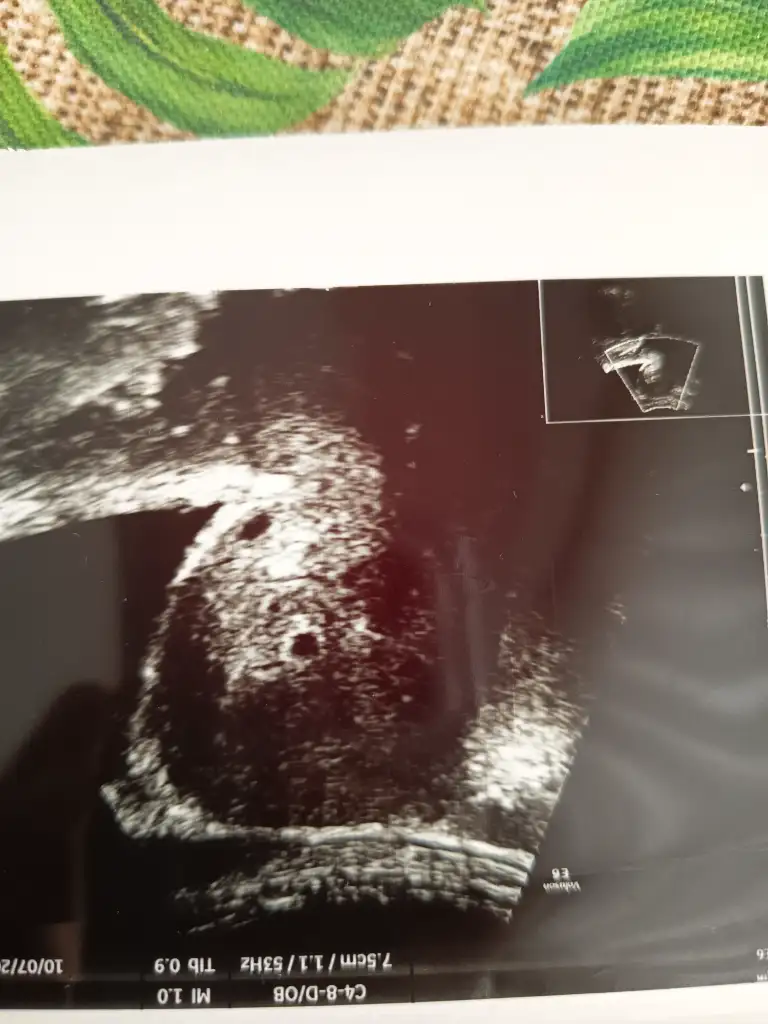

bunu burdan kimse anlamaz ki doktor bilir sadeceArkadaşlar sizce kesenin yukarsinda görülen siyah alan nedir bilgisi olan varmı hiç doktor bişey demedi ama kafama takıldı

Tamamdır teşekkür ederimDoktor olumsuz bir durum olsa mutlaka belirtirdi. Benim de ilk ultrason görüntüm böyle